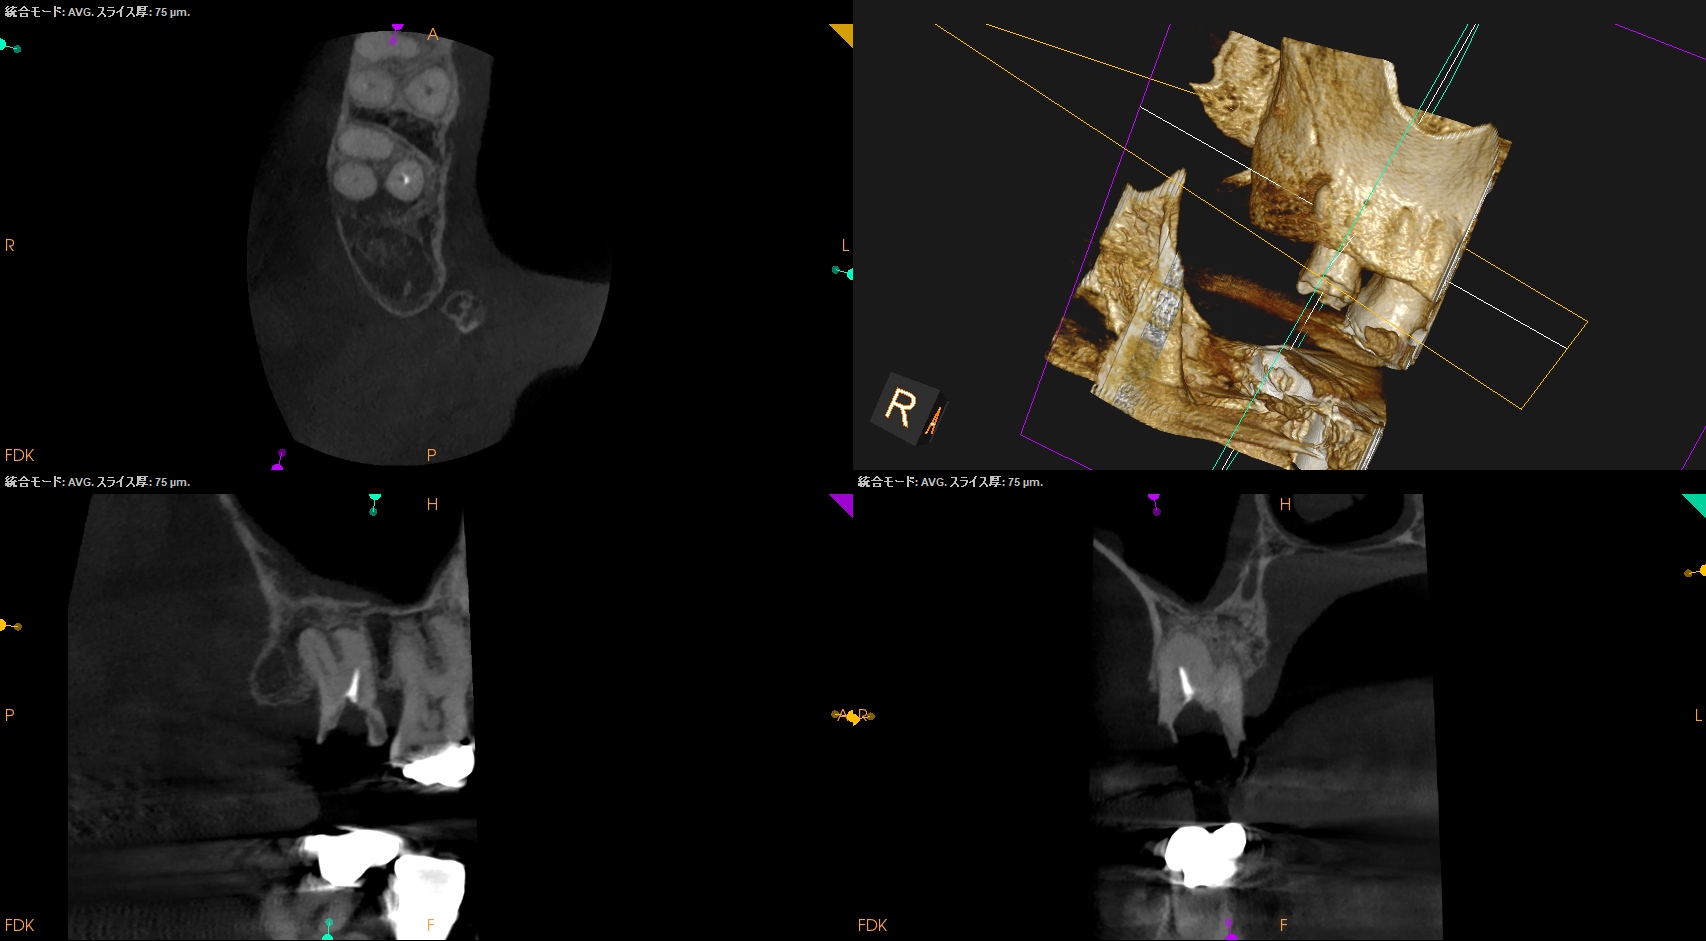

根尖病変があり頬側歯槽骨が穿孔しているDB, レンツロが破断しており根尖病変があるPをSelectiveに再根管治療するという方針を術前に決定した。

#2 Re-RCT(2026.3.9)

それの除去に没頭?すると時間を取られるのでまずはDBからだ。

が、根管口がどの辺りに存在するか?判然としない。

そこでMBのGutta Percha Pointを目印にDBを探索することにした。

SXで上部を拡大した後に根管形成した。

その後、Pだ。

レンツロは以下のようにして除去した。

全長8mmのレンツロは除去された。

まさに秒殺だ。

その後、以下のように形成した。

根管充填後にPA, CBCTを撮影した。

DB

P

問題はないだろう。